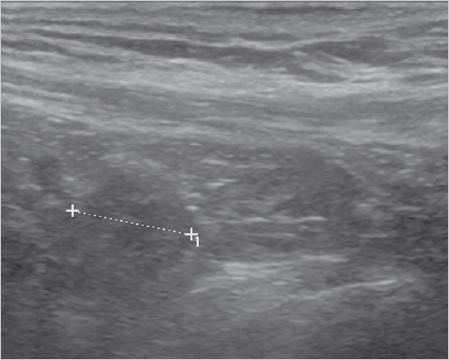

Fig. 3.4 Dynamic ultrasound scan with typical appearance of the bulge, which is diagnostic of sportsman’s groin.

In addition to an accurate history and physical examination, ultrasonography plays a very important role. The sliding layers in the groin region can be examined and the local bulge (

Fig. 3.4) of the posterior wall of the inguinal canal during static and dynamic examination (when the patient strains) can be detected.80 This finding is diagnostic in conjunction with the clinical symptoms. Correctly performing and interpreting an ultrasound of the groin requires much experience and practice.